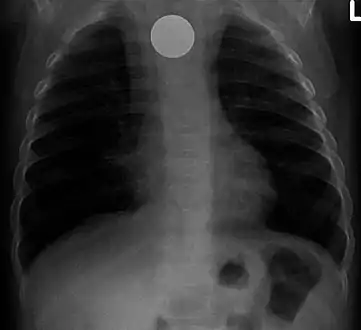

An endoscopy image of the stomach, showing a foreign body in the form of a toothbrush.

One of the most common locations for a foreign body is the alimentary tract.

It is possible for foreign bodies to enter the tract from the mouth or rectum.

Both children and adults experience problems caused by foreign objects becoming lodged within their bodies. Young children, in particular, are naturally curious and may intentionally put shiny objects, such as coins or button batteries, into their mouths. They also like to insert objects into their ear canals and nostrils.[1] The severity of a foreign body can range from unconcerning to a life-threatening emergency. For example, a coin causes local pressure on the tissue but generally is not a medical emergency to remove. A button battery, which can be a very similar size to a coin, generates hydroxide ions at the anode and causes a chemical burn in two hours.[2] An ingested button battery that is stuck in the esophagus is a medical emergency. In 2009, Avolio Luigi and Martucciello Giuseppe showed that although ingested nonmagnetic foreign bodies are likely to be passed spontaneously without consequence, ingested magnets (magnetic toys) may attract each other through children's intestinal walls and cause severe damage, such as pressure necrosis, perforation, intestinal fistulas, volvulus, and obstruction.[3]